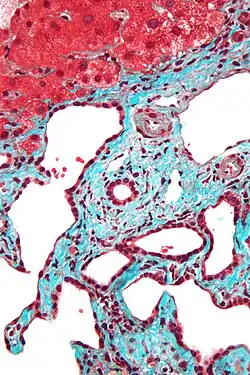

Histopathology of a bile duct hamartoma, high magnification, H&E stain. It shows typical features of bile duct hamartoma: Small to medium sized, irregularly shaped bile ducts lined by bland cuboidal epithelium (may also be flattened). Prominent intervening collagenous stroma. Bile ducts containing eosinophilic debris (may also contain inspissated bile) -

Micrograph of a bile duct hamartoma. Trichrome stain. Intermediate magnification -

Micrograph of a bile duct hamartoma. Trichrome stain, high magnification -